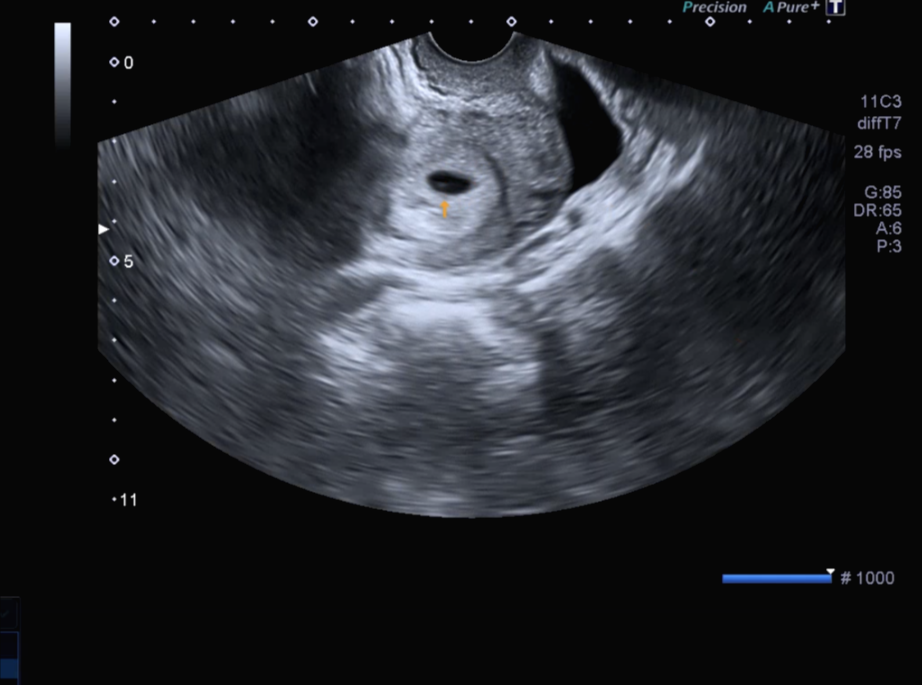

아직은 네가 너무 작은 존재라 배 초음파로는 너를 볼 수 없다고 하더라, 질 초음파를 통해 아기집을 처음 확인했단다.

의사 선생님께서 지금 아기집은 10mm 정도가 된다고 알려주셨어. (10mm 맞나?)